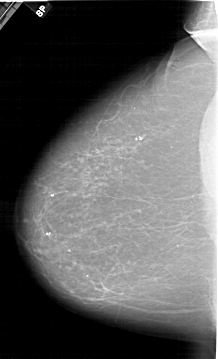

A_1597_1.RIGHT_CC

RIGHT_MLO LINES 6346 PIXELS_PER_LINE 3781 BITS_PER_PIXEL 12 RESOLUTION 43.5 OVERLAY